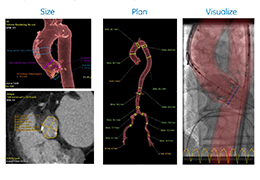

Coregistration of MRI with EEG & MEG

Coregistration of MRI with EEG & MEG

For an easy superposition of the results of source analysis with individual EEG and MEG data, BrainVoyager provides an interactive link to BESA (Brain Electrical Source Analysis). The bidirectional connection of the two programs allows for source seeding from fMRI clusters with one mouse click.